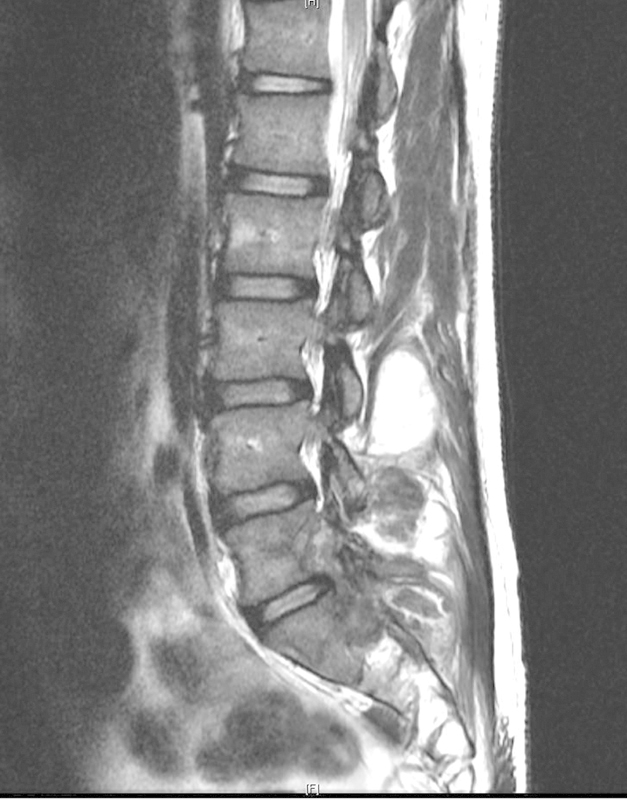

研究设计案例报告。目的:本研究的目的是报道腰椎骨痛风的发生。方法通过一个病例报告来说明脊柱痛风的要点,我们简要回顾了痛风的文献,因为它与骨科和脊柱表现以及管理指南有关。结果:本病例报告详细描述了一名24岁男性腰椎痛风病史和3年进行性背痛的重大临床发现。结论高怀疑指数有助于腰痛或有痛风病史的神经系统疾病的诊断。既往痛风史(尤其是痛风石)、高尿酸血症和影像学特征有助于临床医生诊断脊柱性痛风。早期诊断有可能避免手术干预的需要。

Study Design Case report. Objective The objective of this study is to report the occurrence of tophaceous gout in the lumbar spine. Methods Using a case report to illustrate the key points of gout in the spine, we provide a brief review of gout in the literature as it relates to its orthopedic and spinal manifestations as well as guidelines for management. Results This case report details the occurrence of a large and clinically significant finding of tophaceous gout in the lumbar spine in a 24-year-old man with a known history of gout and a 3-year history of progressive back pain. Conclusion A high index of suspicion can assist in diagnosis of patients presenting with back pain or neurologic findings with a history of gout. A previous history of gout (especially the presence of tophi), hyperuricemia, and the radiological characteristics presented here should aid the clinician in making the diagnosis of spinal gout. Early diagnosis has the potential to prevent the need for surgical intervention.